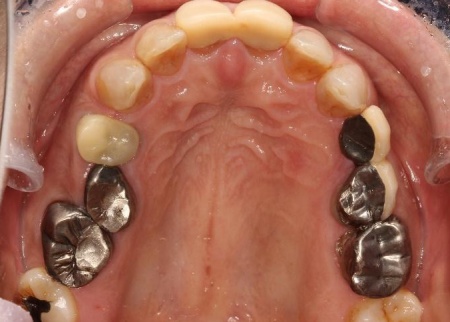

40代女性 乱れた歯並びと不安定な噛み合わせを矯正治療と被せ物で改善した症例

拝見したところ、もともと左上の歯と左下前歯が欠損しているうえ、奥歯の欠損も進んでいたため、噛み合わせが低くなっていました。

奥歯が噛み合わない状態になったことで、上前歯が前方に押し出され、出っ歯のようになっています。

また、下の歯は歯根だけが残る「残根」もあり、全体的に噛み合わせが不安定です。

さらに食いしばりの習慣があることから、残っている歯や顎関節に過度な負荷がかかっていると考えられます。